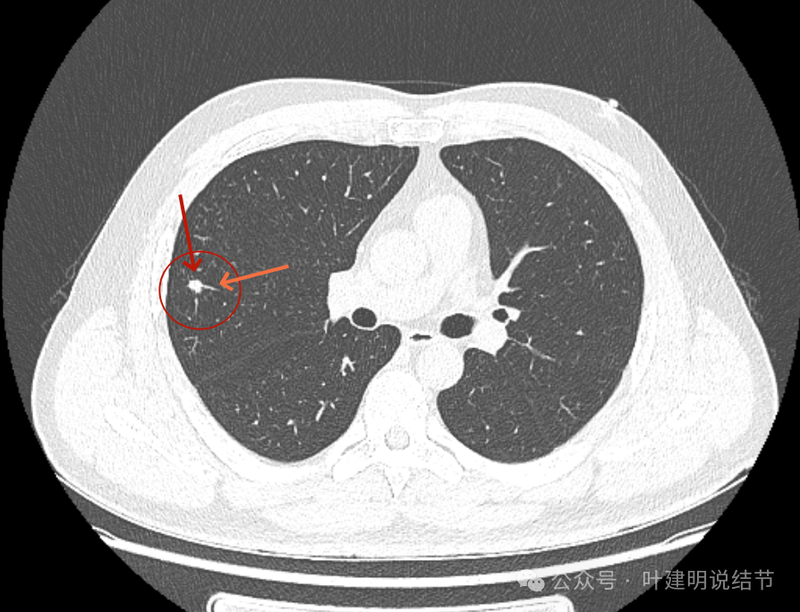

2022年10月主病灶处没有异常。

2022年时右中叶处本来就有的。

右上这个结节实性,有血管征的样子,整体轮廓较清,如果从单次来看,是要考虑恶性可能性稍大些的,何况对比2022年时此灶不明显,那是新增的。但我觉得总体上看,倾向良性的一些:1、两肺,尤其是右中叶有多发斑点状实性小结了,较为散在,且对比2022年时无明显进展,说明肺部存在感染性的情况过,他处是遗留有慢性炎或肉芽肿性病变的基础在的,那么主病灶也是同样性质的可能性就增大了;2、冠状位与矢状位看,病灶的瘤肺边界不是很清楚,不像横断面上清楚,说明炎性的可能性是有的;3、实性病灶,但在纵向看,邻近血管并没有受到牵拉影响,没有形成血管弯征,说明收缩力或侵袭性不够。再加上病灶仍小,我的想法是考虑良性可能性大,并建议先4-6个月再复查下,期间也可试试口服莫西沙星消炎10-12天,若更进一步,也可查查结核与隐球菌方面的化验。意见供参考!